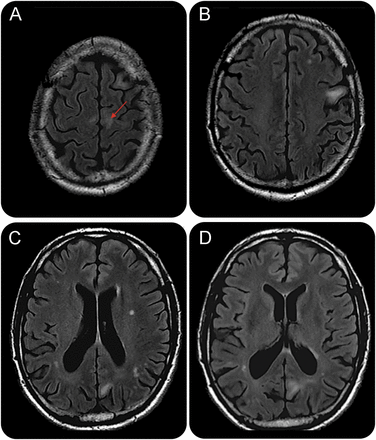

一个54岁的人,15个月后同种异体的外周血干细胞移植(ASCT)脊髓发育不良,开发连续的右脚不自觉的抽搐。脑电图是暗示epilepsia partialis连续(EPC) (图1)。脑部核磁共振成像显示增加信号在左侧中央白质(图2)。血评估发现白细胞3400,500个淋巴细胞,脑脊液PCR JC病毒是积极的(250拷贝/毫升)与正常cyto-biochemical评估。本例符合诊断标准的渐进多焦点的脑白质病(PML)。1PML由EPC异常显示2和ASCT构成一种罕见的并发症。

图2

脑核磁共振

轴向fluid-attenuated反转恢复图像:(一)hyperintensity离开中央皮层下白质(箭头);(罪犯)多病灶的不对称nonconfluent白质病变,无质量效应。